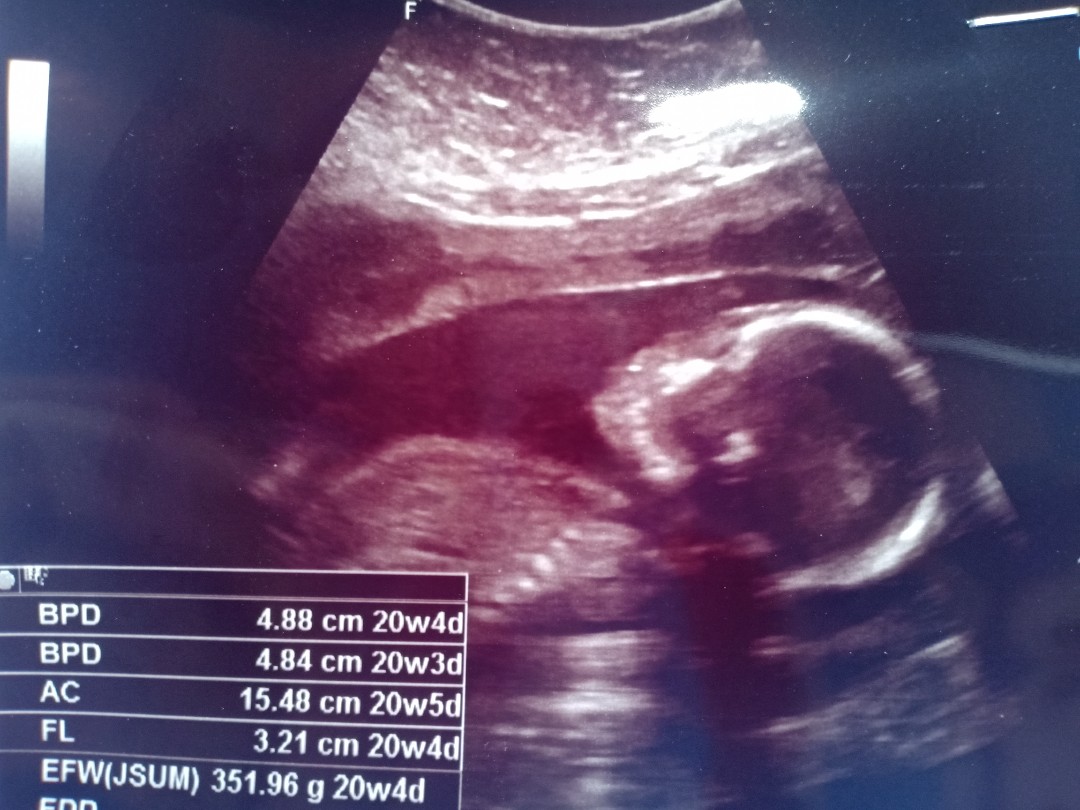

17 พฤศจิกา ชายจ้า

22 พฤศจิกายน คร่า

บ้านนี้3 พฤศจิ 🥰

บ้านนี้ 13 พ.ย ค่ะ

1 พ.ย ค่ะ ผู้ชายย

7 พฤศจิกายนคะ

10 พฤศจิกายน จ้า

16 พ. ย 63 ค่ะ

8/11/63 น้องชายค่ะ

บ้านนี้2พ.ยจ้า